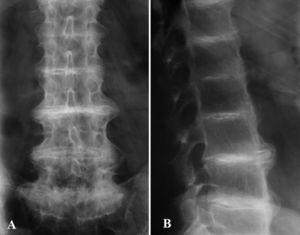

La hematimetría, recuento, fórmula, velocidad de sedimentación globular, y perfil bioquímico fueron normales o negativos. El perfil hepático mostró un leve aumento de transaminasas y gammaglutamiltransferasa, y en la ecografía se confirmó una esteatosis hepática de probable origen alcohólico. En orina de 24 h se demostró la presencia de ácido homogentísico muy elevado (5.616,0 mg/24 h [N ≤ 10,0 mg/24 h]). En el estudio radiográfico de la columna lumbar se apreciaron imágenes de osteoporosis difusa, calcificación del ligamento vertebral anterior, osteofitosis anterior, disminución de la altura de las vértebras lumbares y calcificación de todos los discos intervertebrales (fig. 5). La radiografía de la rodilla izquierda mostraba fenómenos de calcificación articular. Se realizó un estudio gammagráfico que demostró la presencia de un refuerzo intervertebral lumbar e imágenes de hipercaptación en la articulación del hombro y de la rodilla. Estos hallazgos gammagráficos en este paciente han sido previamente publicados por Cortés-Hernández et al 3. Se instauró tratamiento con complementos de vitamina C, (1.000 mg/día) y el paciente manifestó una discreta mejoría de sus síntomas articulares.

Fig. 5.--Radiografía simple anteroposterior (A) y lateral (B). Estrechamiento y calcificación de las articulaciones intervertebrales. Pérdida de la lordosis fisiológica.

Los hallazgos radiológicos, como en nuestro paciente, son característicos si no patognomónicos 2. Hay un estrechamiento progresivo generalizado, calcificación, osificación, e incluso fusión de los espacios intervertebrales 8. A diferencia de las espondilitis, raramente se afectan las articulaciones sacroilíacas. En casos aislados se han realizado estudios gammagráficos con hallazgos equivalentes a cualquier otra artropatía degenerativa, aunque con algún rasgo característico 3.